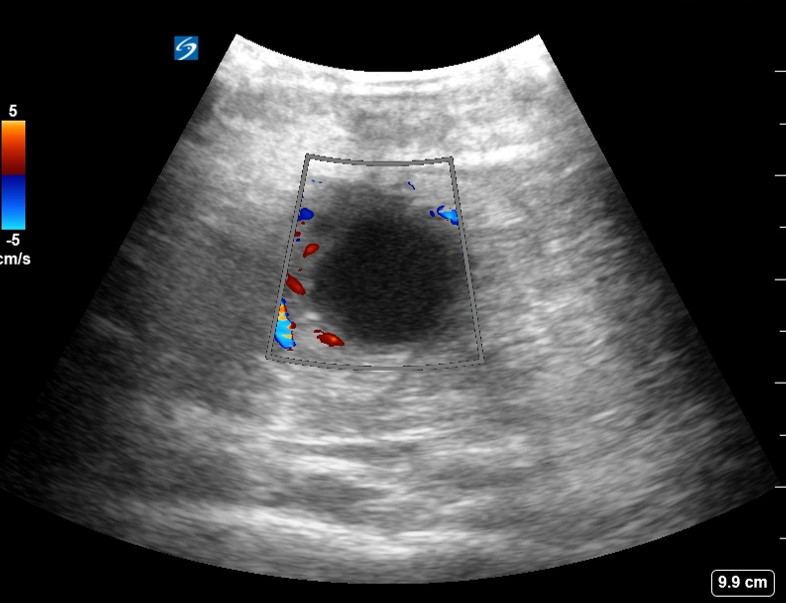

From www.criticalcare-sonography.com

Deep buttock abscess. Critical Care Sonography Abscess Buttock Swelling or redness near the anus. A buttock abscess is a localized collection of pus within the tissue of the buttocks, usually resulting from an infection. Bacteria, including staphylococcus aureus, often referred to as staph, are likely to blame. Symptoms may include pain, constipation, or fever. These are possible signs of an anorectal abscess: Most anal abscesses are a. An. Abscess Buttock.